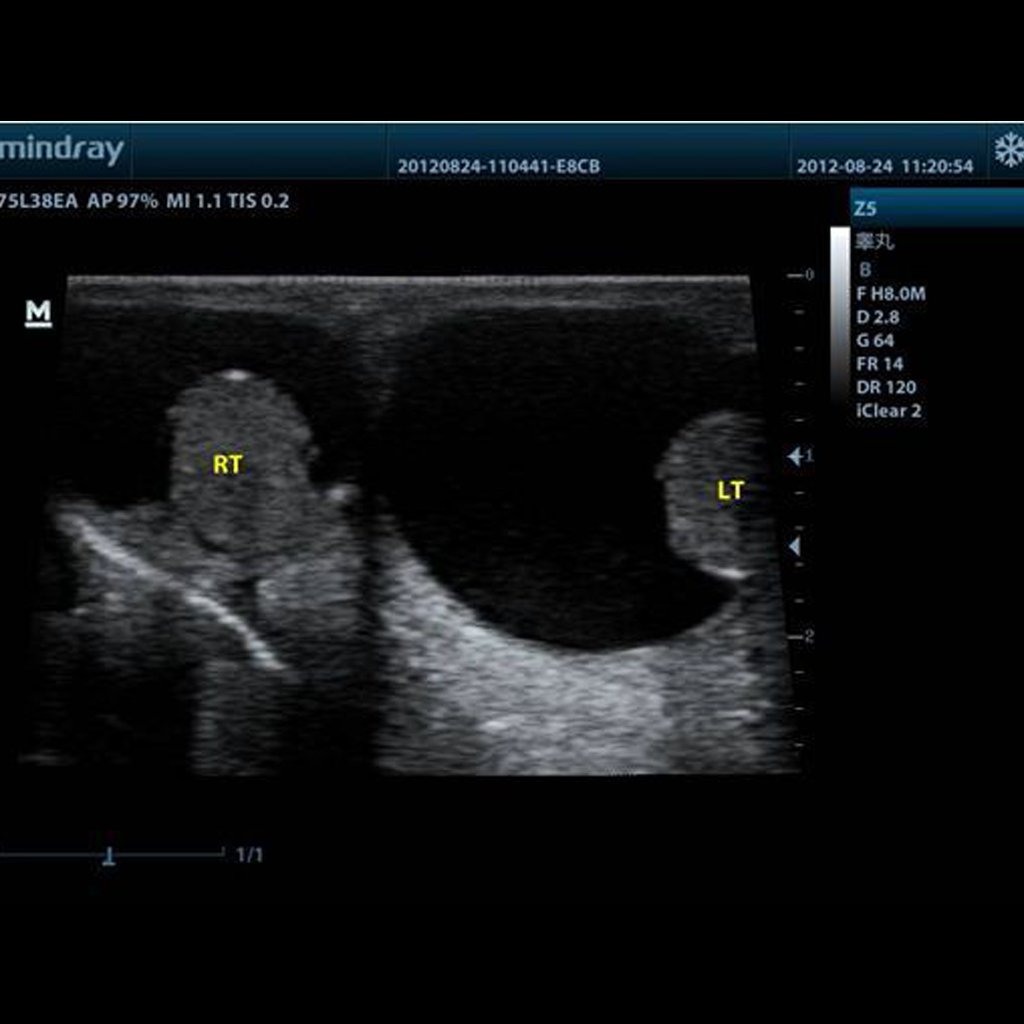

Технология, помагаща при визуализирането на по-големи анатомични структури или интересни региони чрез разширяване на полето за изобразяване отвъд стандартната правоъгълна форма, често наподобяваща трапец. Тя позволява получаването на по-изчерпателни изображения, особено полезни в случаи когато е необходима по-широка перспектива за точна диагноза или оценка.